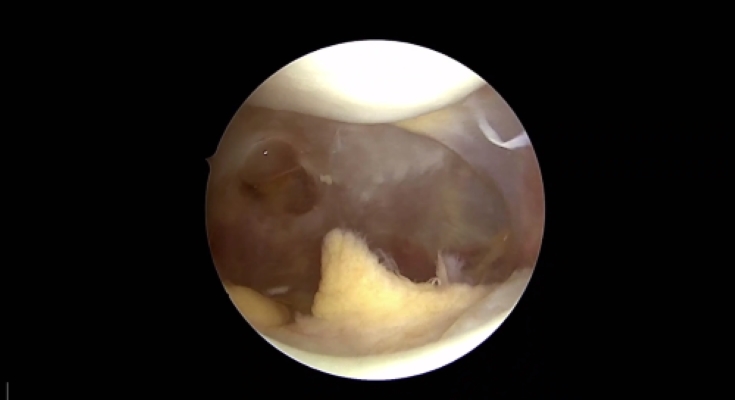

Erkenntnisse zur Wirkung der Produktdosis bei Autologer Chondrozytentransplantation bei Knorpeldefekten im Kniegelenk – Überblick der CO.DIS-Studie

Knorpelzelltranplantation an der Patella vs. Femur - Klinische Ergebnisse und Erfolgsraten im Vergleich

Vorteile der Autologen Chondrozytentransplantion mit Spheroid-Technologie vs. Mikrofrakturierung – Ergebnisse einer Nicht-Unterlegenheitsstudie nach 36 Monaten (CO.WISI)

Sicherheit und Wirksamkeit der Autologen Chondrozytentransplantation bei Jugendlichen im Vergleich zu jungen Erwachsenen (PIP-Studie)

Wichtigste Studienergebnisse aus dem Zulassungsprozess des Produktes Spherox für die zentrale europäische Zulassung – Überblick und Diskussion